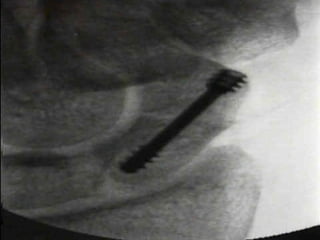

Management

 DeMaagd and Engber showed 11 of 12 patients with proximal

pole fractures healed with Herbert screw

 Retting and Raskin had 100% union in 17 cases with Herbert

screw

 If fragment too small then K-wires can be used

 Unstable fractures best treated with compression

screw fixation

– >1mm displacement

– Fragment angulation

– Abnormal carpal alignment

 With advent of percutaneous techniques of

cannulated screws under flouroscopic control trend

towards operative management

Management  DeMaagd andEngber showed 11 of 12 patients with proximal pole fractures healed with Herbert screw  Retting and Raskin had 100% union in 17 cases with Herbert screw  If fragment too small then K-wires can be used

Management of waistfractures  Most stable fractures can be treated with below elbow thumb spica  Unstable fractures best treated with compression screw fixation – >1mm displacement – Fragment angulation – Abnormal carpal alignment  With advent of percutaneous techniques of cannulated screws under flouroscopic control trend towards operative management